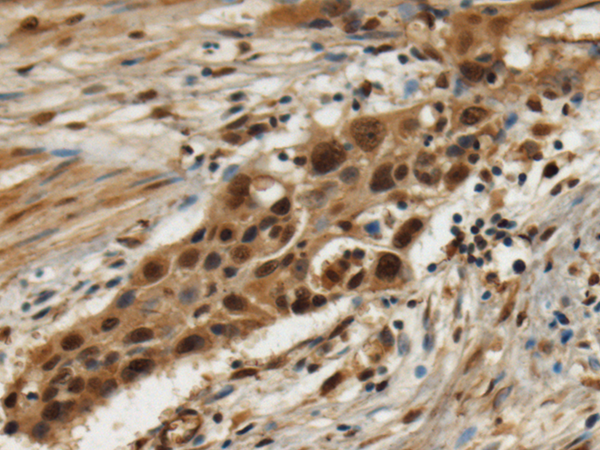

IHC positive control: |

Human tonsil and Human esophagus cancer |

IHC Recommend dilution: |

100-300 |